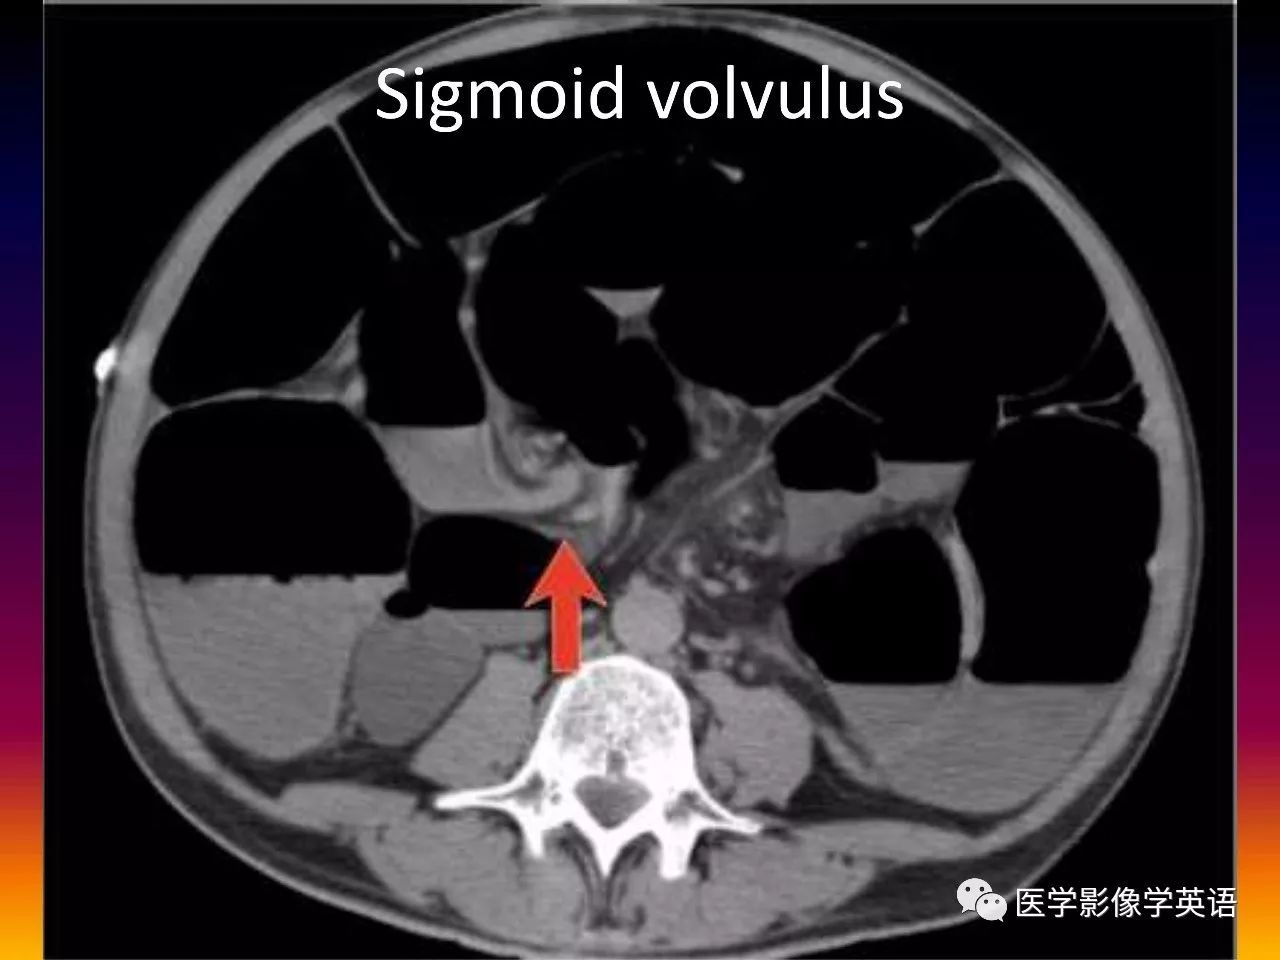

85. Sigmoid volvulus

86. Sigmoid volvulus

45. Volvulus Gastric volvulus Organo-axial Greater curvature above lesser curvature Mesentero-axial Gastric antrum above gastric fundus Midgut volvulus Malrotation (SMV to the left of SMA) Whirl sign Colonic volvulus Sigmoid Whirl sign Cecal Whirl sign